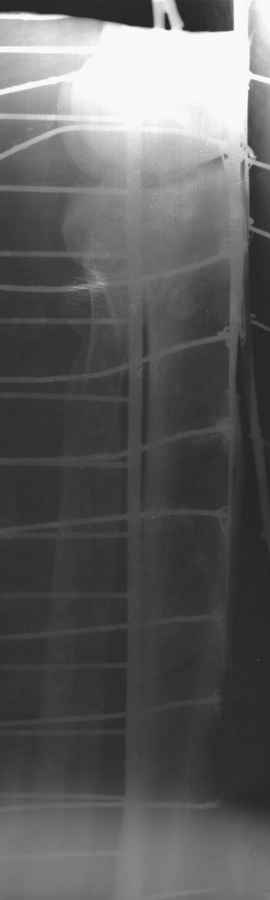

Пациенту сделали КТ - ухитрились сделать на шине Белера (не давал положить прямую ногу) - срезали передний отдел. Планируется на пятницу (24.12) на операцию - синтез длинной мыщелковой LCP-пластиной Synthes :). Отек ближе к слову умеренный (окружность голени +4 см по сравнению со здоровой). КТ и снимок на вытяжении прилагаются.

Уважаемые коллеги! В прошлую пятницу больной прооперирован - как и планировалось мыщелковая LCP от ChM. Малоинвазивно не получилось - один большой доступ :(. (но с минимальным скелетированием б/б кости). Наружный мыщелок собрали, но по контролю видно, что задне-медиальный отдел метаэпифиза смещен. Фиксировать не стали (?). 4-е сутки после операции - по м/тканям без проблем. Дополнительная иммобилизация синтетическим тутором.

P. S. перелом диафиза на контроле не совсем захвачен, но проблем там нет. Приношу извинения за низкое качество Р-грамм - выполнены на сканере (фотоаппарат не работает :)) .

Трудно поверить, что разрекламированная Ортопедическая школа Восточной Украины позволяет такие странные снимки? На прямом снимке сохранен общий контур плато, но не известна судьба импрессии суставной поверхности. На полубоковой?, оставлен без репозиции задне-медиальный отдел, и навряд ли после такой фиксации можно удовлетвориться результатом.

Представленные снимки не информативны, нужны отдельные качественные снимки коленного сустава и голени без ротации.